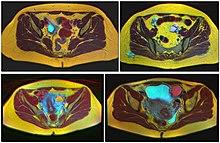

Ovarian cysts are usually diagnosed by ultrasound, CT scan, or MRI, and correlated with clinical presentation and endocrinologic tests as appropriate.[10]

Follow-up imaging in women of reproductive age for incidentally discovered simple cysts on ultrasound is not needed until 5 cm, as these are usually normal ovarian follicles. Simple cysts 5 to 7 cm in premenopausal females should be followed yearly. Simple cysts larger than 7 cm require further imaging with MRI or surgical assessment. Because they are large, they cannot be reliably assessed by ultrasound alone; it can be difficult to see posterior wall soft tissue nodularity or thickened septation due to limited ultrasound beam penetrance at this size and depth. For the corpus luteum, a dominant ovulating follicle that typically appears as a cyst with circumferentially thickened walls and crenulated inner margins, follow up is not needed if the cyst is less than 3 cm in diameter. In postmenopausal patients, any simple cyst greater than 1 cm but less than 7 cm needs yearly follow-up, while those greater than 7 cm need MRI or surgical evaluation, similar to reproductive age females.[11]

For incidentally discovered dermoids, diagnosed on ultrasound by their pathognomonic echogenic fat, either surgical removal or yearly follow up is indicated, regardless of patient age. For peritoneal inclusion cysts, which have a crumpled tissue-paper appearance and tend to follow the contour of adjacent organs, follow up is based on clinical history. Hydrosalpinx, or fallopian tube dilation, can be mistaken for an ovarian cyst due to its anechoic appearance. Follow-up for this is also based on clinical presentation.[11]

For multiloculate cysts with thin septation less than 3 mm, surgical evaluation is recommended. The presence of multiloculation suggests a neoplasm, although the thin septation implies that the neoplasm is benign. For any thickened septation, nodularity, vascular flow on color doppler, or growth over several ultrasounds, surgical removal may be considered due to concern of cancer.[11]